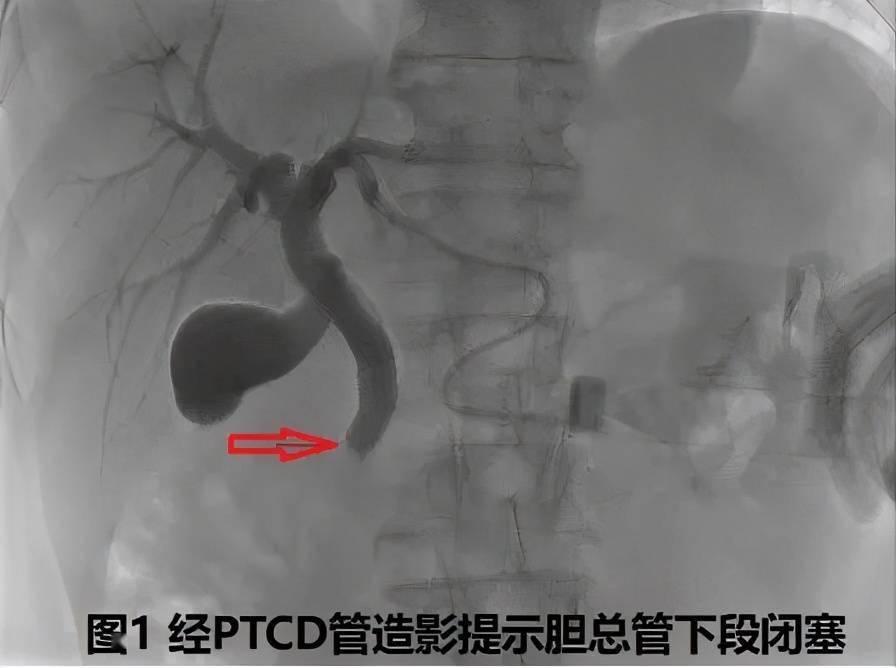

(数字减影血管造影技术)引导下经皮经肝途径胆道钳夹活检术(如下图示)